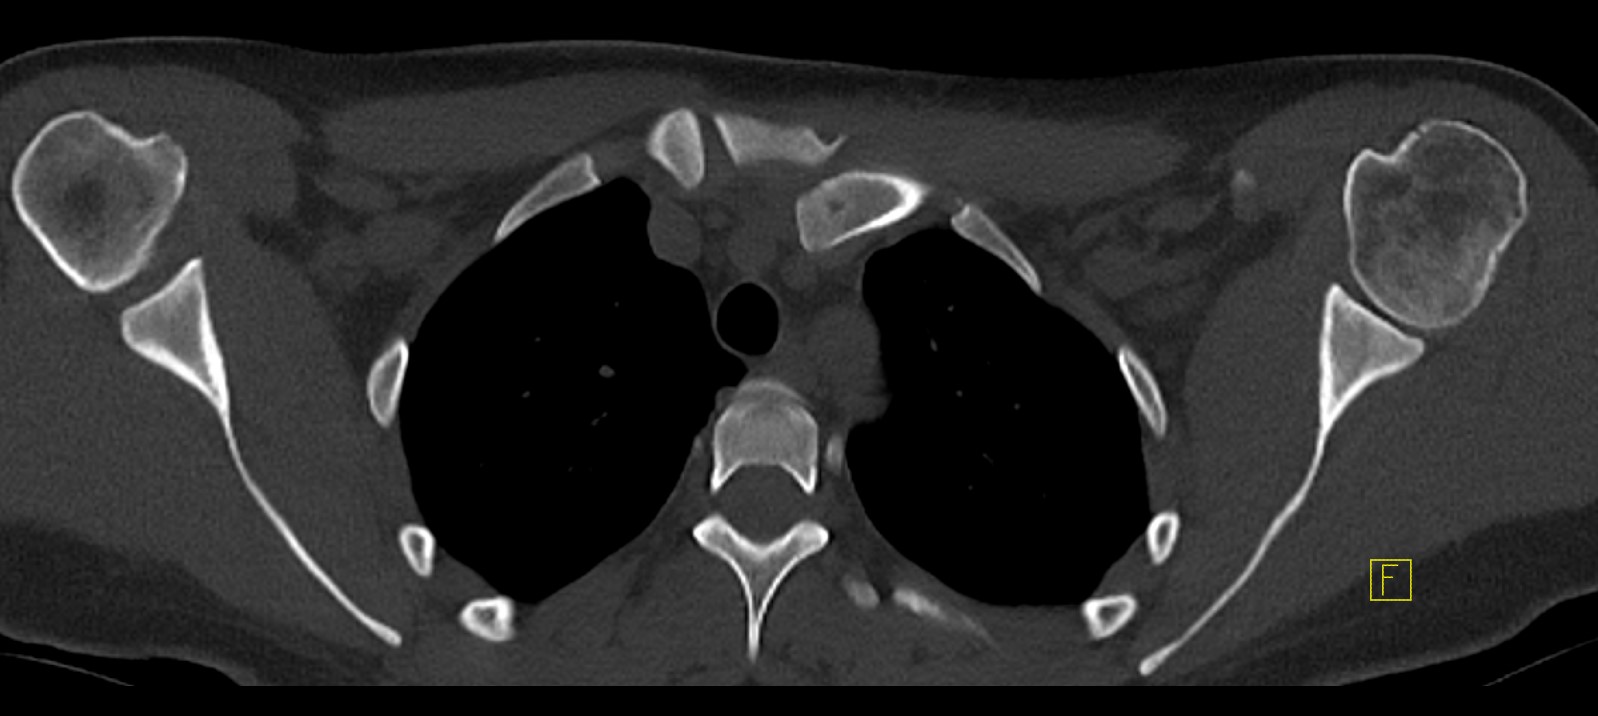

CT scan

Left posterior SCJ dislocation with pre- and post angiogram

Severe left posterior SCJ dislocation with subclavian vein compression